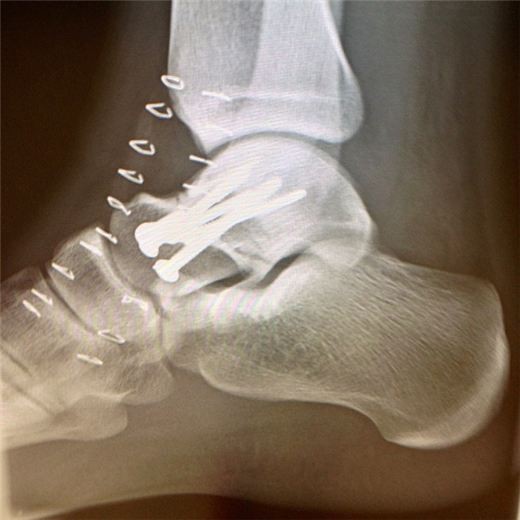

7 screws n a Metal plate, Cast off January 7th!